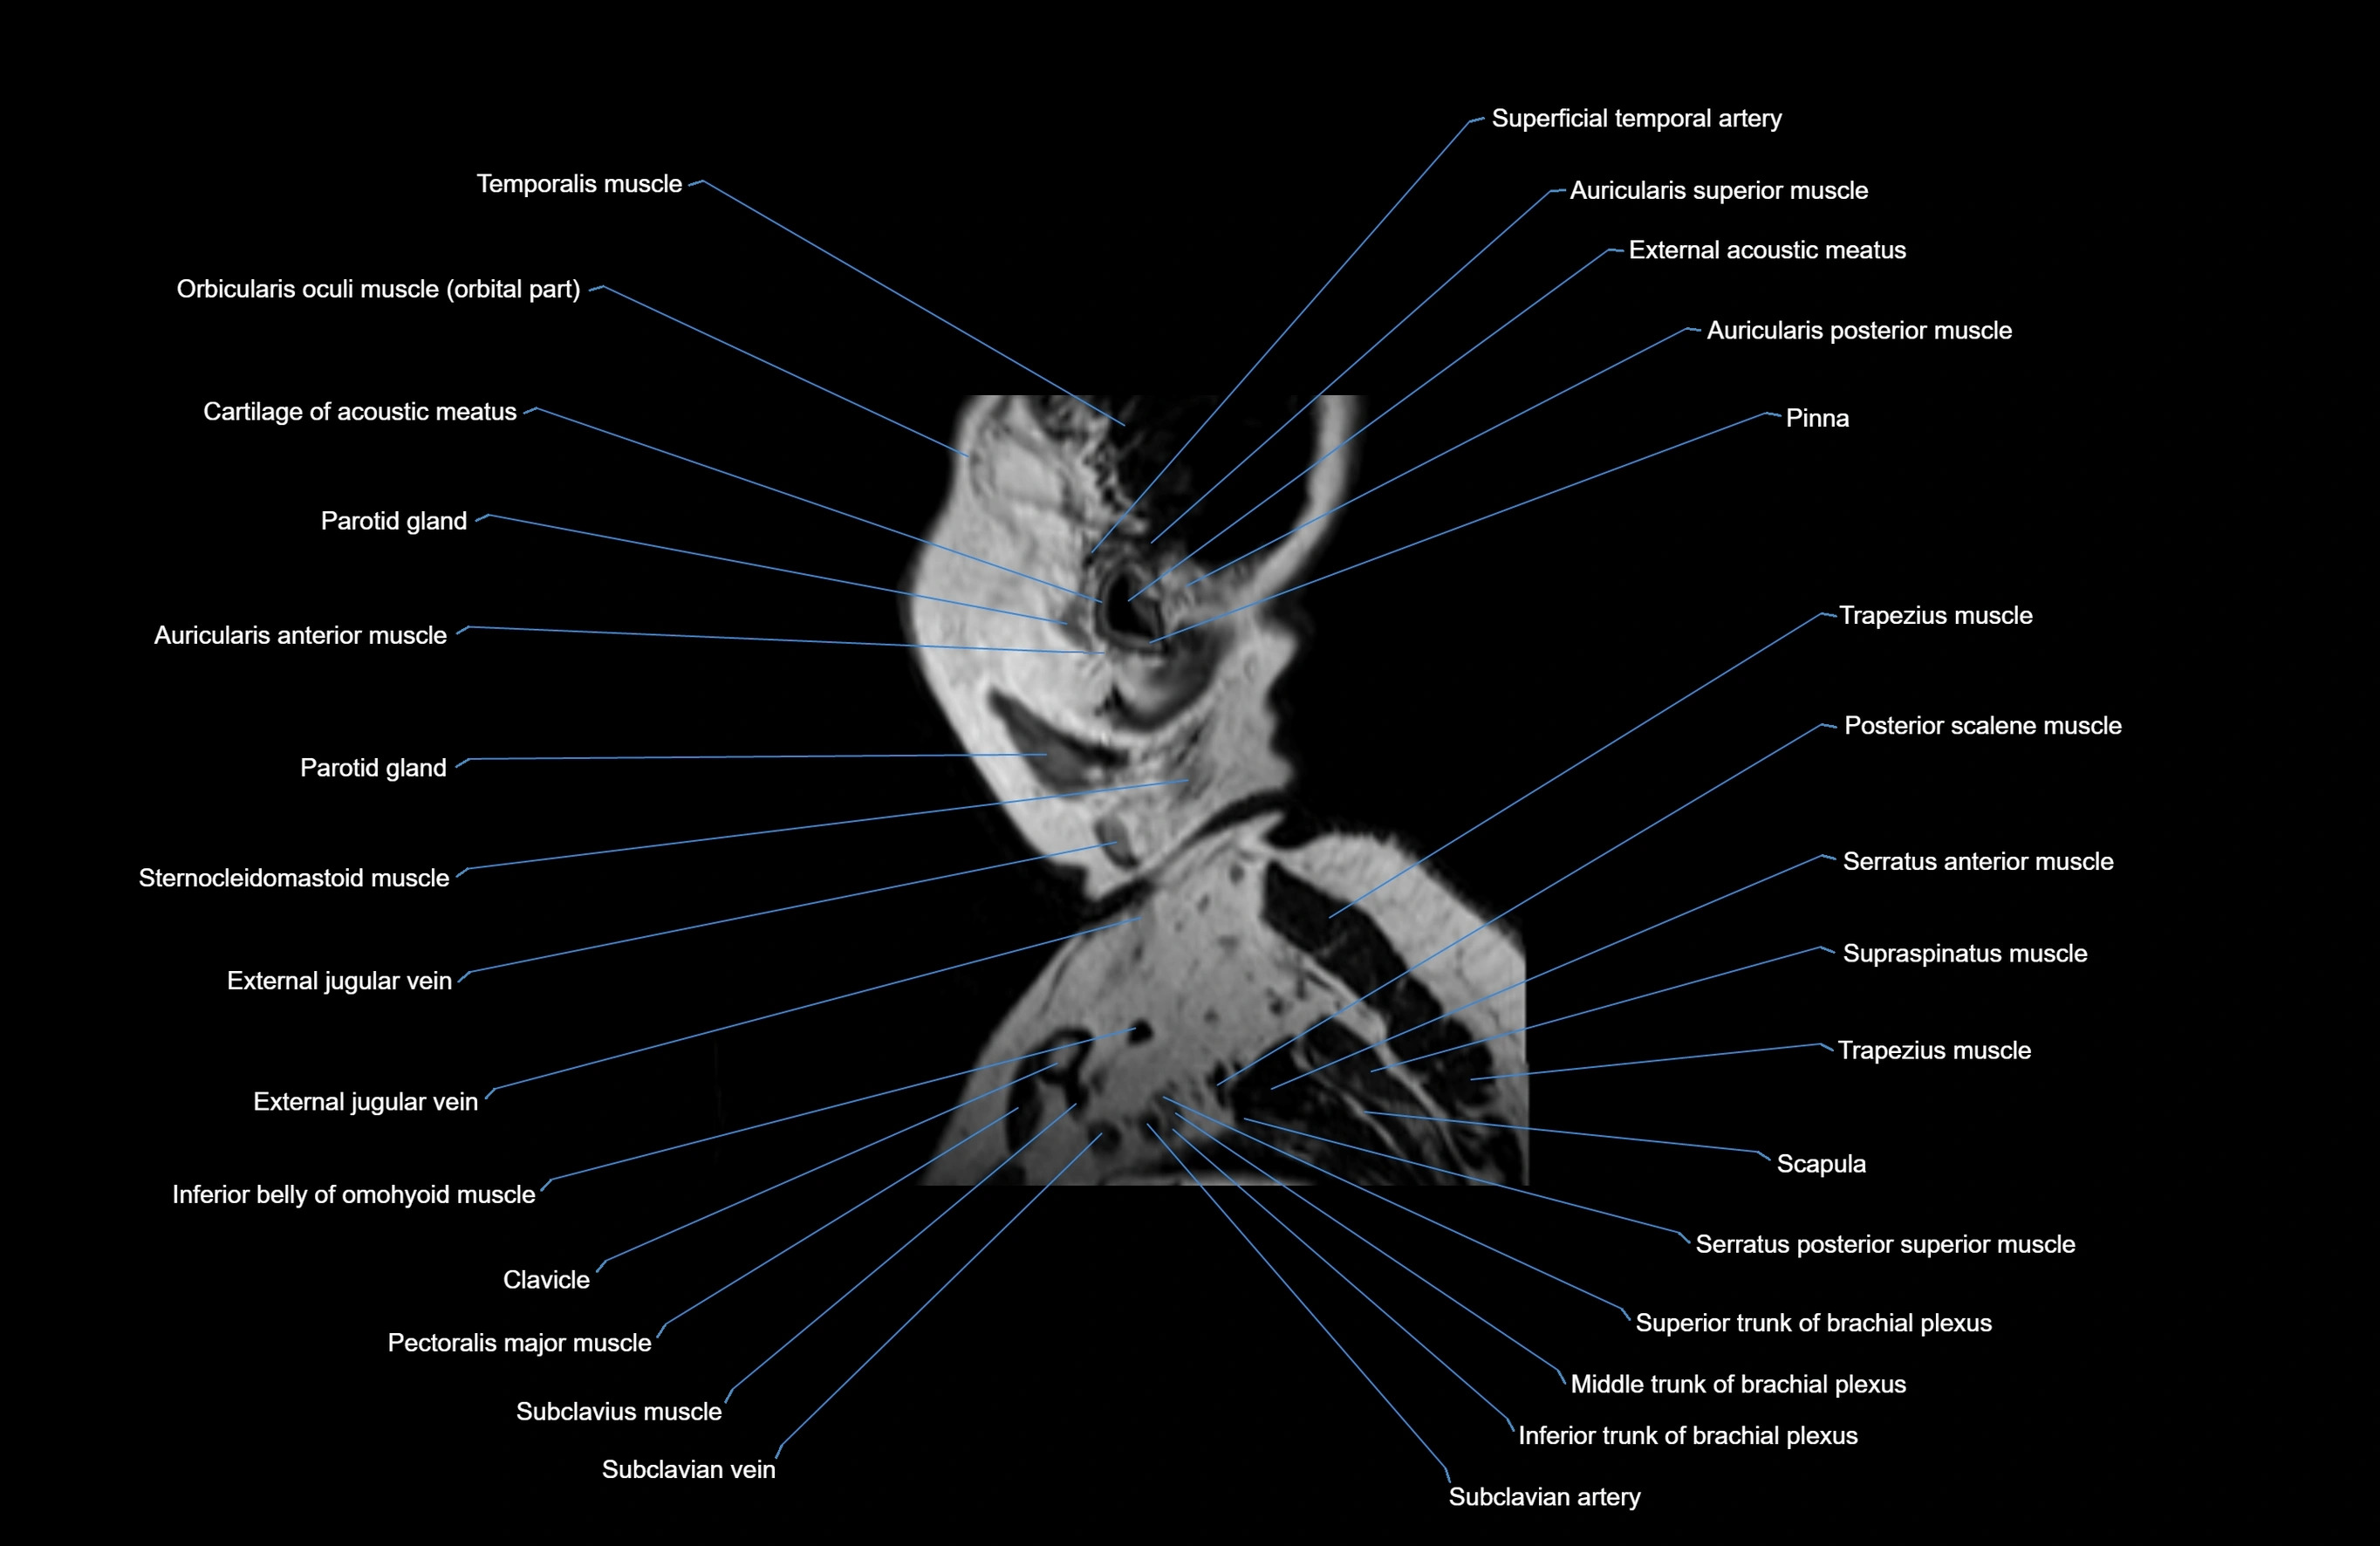

MRI images